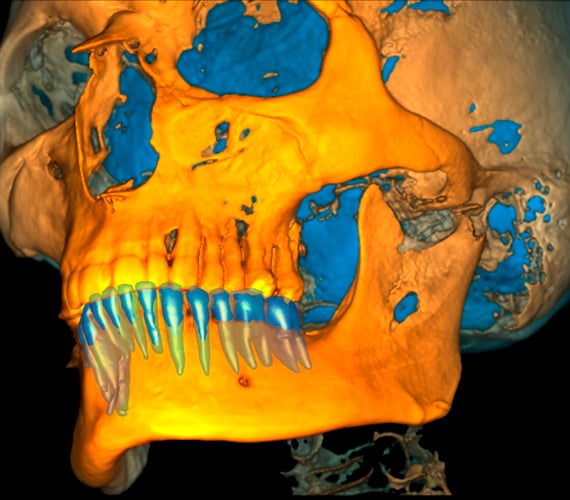

Romexis provides an extensive toolkit for segmenting volumetric CBCT data. The entire volume can be converted to an STL model. Individual teeth, the mandible and maxilla, airways, sinuses and roots can all be segmented, saved and exported as STL files from the software for further orthodontic or prosthetic planning and 3D printing.

CBCT images are ideal for orthodontic diagnoses and the Romexis software makes it easy to analyse skeletal symmetry, detect unerupted and supernumerary tooth positions, as well as identify root resorption and orientation accurately. The software can also create cephalometric images and panoramic views from CBCT images to be used for cephalometric analyses.